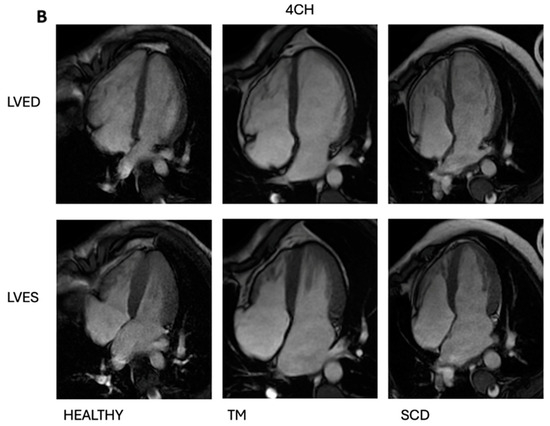

2.4. Magnetic Resonance Imaging (MRI)